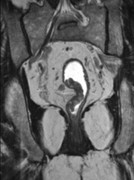

[单选题]患者 男,38岁,感觉左髋部疼痛,并逐渐加重,体检:左髋部明显肿胀压痛,无明显发热,请选择最佳诊断()A.骨巨细胞瘤B.纤维肉瘤C.骨肉瘤D.软骨肉瘤